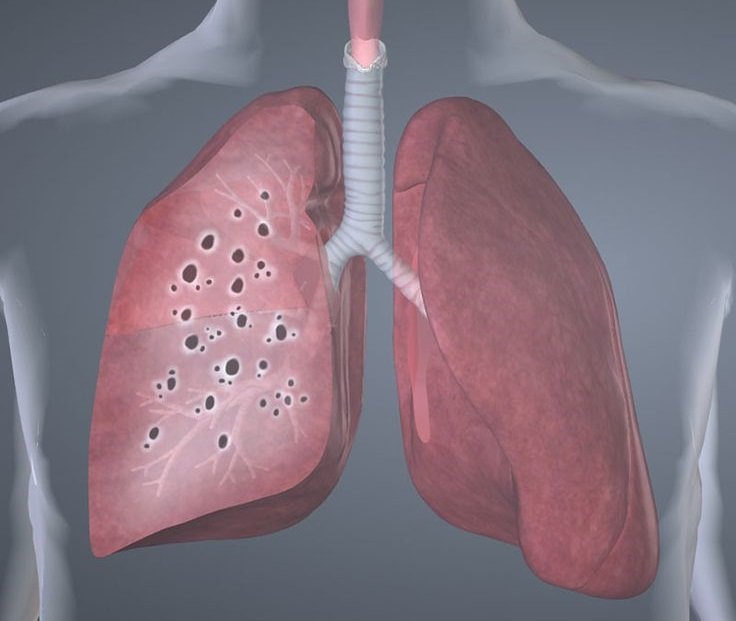

Саркоидоз легких — это системная патология органов дыхания, при которой происходит поражение легочных тканей и образование гранулем — небольших воспалительных участков (гранулематозное воспаление) в виде плотных узелков – саркоидных гранулем. Эта болезнь классифицируется как доброкачественный гранулематоз.

Внешне гранулемы при саркоидозе схожи с туберкулезными, но для узелков саркоидных не является характерным формирование казеозного некроза и присутствие бактерий туберкулеза. По мере развития гранулемы проявляются тем, что могут сливаться в большие очаги. Такие очаги в каком-либо органе срывают его работу и ведут к проявлениям симптоматики саркоидоза.

Обычно это заболевание имеет полиорганное течение. Саркоидоз (Sarcoidosis) поражает альвеолярную ткань, и начинается развитие интерстициального пневмонита или альвеопита, с дальнейшим формированием саркоидных гранулем в области субплевральных и перибронхиальных тканей и меджолевых бороздах. Исходом заболевания бывают фиброзные аномалии пораженного органа или рассасывание гранулем (превращается в стекловидную массу).